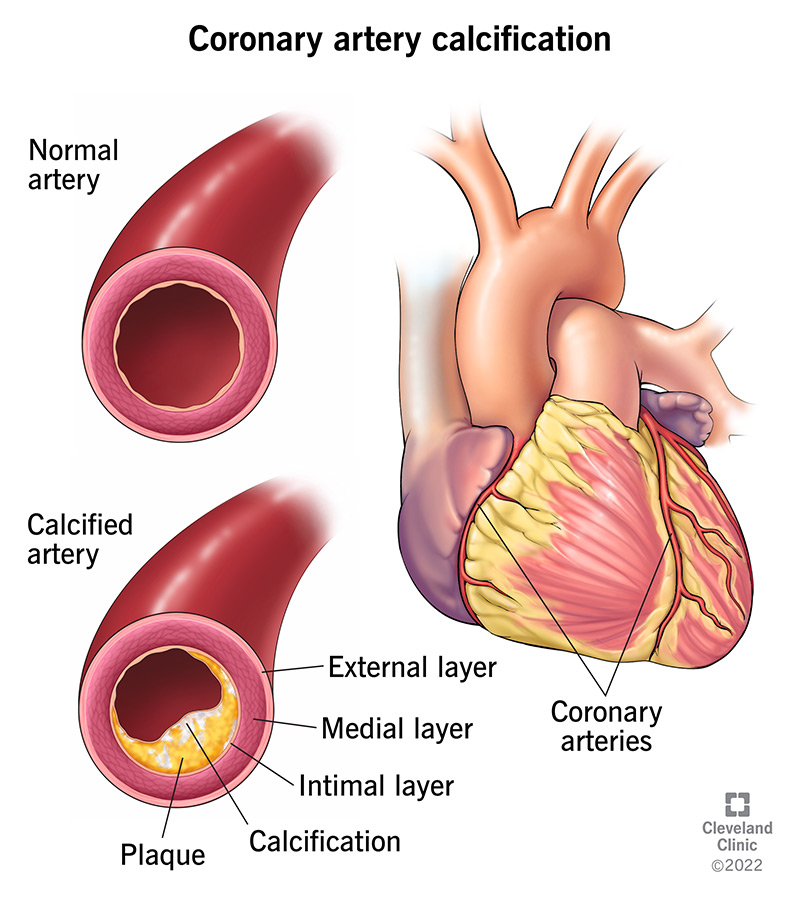

Calcification is just a sign of coronary atery disease and it can be prevented by lowering risk factors such as smoking, high blood pressure, diabetes, high. You may be able to prevent calcium deposits by monitoring your health and seeing your healthcare provider regularly. If cancer is found, treatment may include.

“pericardial tissue tends to bind calcium ions, which in turn bind phosphate ions, thus encouraging calcification of the prosthetic heart valve. Calcification and stenosis generally affect older adults. The regulated inclusion of this.

Aortic valve calcification may be an early sign of heart disease, even if there aren't any other heart disease symptoms. Water filters like ion exchange or reverse osmosis can remove up to 98% of the impurities in hard water, so technically, they can get rid of the calcium, but not all of it. A great and easy way to prevent calcium buildup is by applying a calcium prohibitor or blockerto the pool tiles or glass.